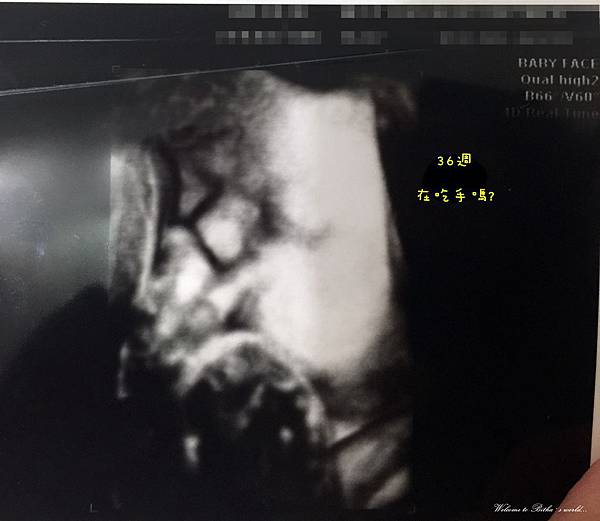

日子飛快來到一個禮拜產檢一次的倒數階段,

下一篇可能就是紀錄寶寶成長的瑣事了(是說要跳過生產那麼刺激的過程嗎?)